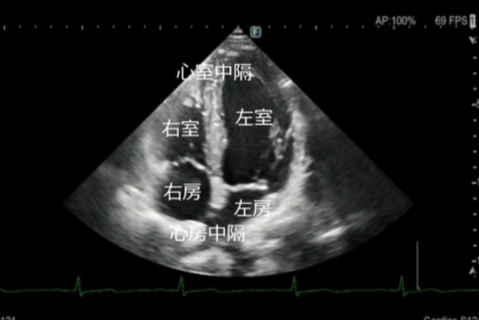

心エコー検査は、超音波を用いて心臓の形や動き、血流の流れを詳しく観察する検査です。

放射線を使用しないため、身体への負担が少なく、安全に繰り返し行うことができます。

エコー(心臓超音波)検査

- このようなことが分かります

弁膜症の評価

心臓の弁(大動脈弁・僧帽弁など)の開き具合や逆流の有無を確認します。

弁の狭窄や逆流の程度を評価し、治療方針の判断に役立てます。 - 心筋の働き(ポンプ機能)の評価

心臓がどのくらいしっかり血液を送り出せているか(収縮機能)を確認します。

心筋梗塞後の機能低下や、拡張型心筋症などの診断にも重要です。 - 心不全の原因検索

息切れやむくみなどの心不全が疑われる場合、その原因が弁膜症によるものか、心筋の

弱りによるものかを詳しく調べます。 - その他

心肥大の有無・心臓内血栓の確認・先天性心疾患の評価・肺高血圧症の推定 など - 検査について

検査時間はおおよそ20~30分程度です。

ベットに横になっていただき、胸にゼリーを塗ってプローブ(探触子)を当て観察します。痛みはありません。

当院では、循環器疾患の早期発見と適切な治療につなげるため、症状がある方は、もちろん、健診等で指摘された方にも心エコー検査を行っております。

お気軽にご相談ください。

超音波診断装置

当院の超音波診断装置(エコー装置)は、高画質で多彩なプローブバラエティと臨床アプリケーションにより、腹部・表在・循環器などの幅広い分野での検査が行えます。当製品はPrecision Imagingを搭載し、超音波画像を形成する信号を処理することにより、組織信号を強調し、生体内組織の境界などの構造視認性を高め、腫瘍部分などがより描出しやすくなっております。